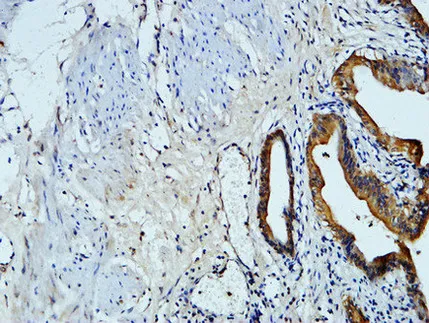

CDX2(14H6)Mouse Monoclonal Antibody

Cat: AMM08595

Size1:50μL Price1:$118

Size2:100μL Price2:$220

Size3:200μL Price3:$380

Application:WB,IF-P,IF-F,ICC/IF,IHC-P

Reactivity:Human,Mouse,Rat

Conjugate:Unconjugated

Optional conjugates: Biotin, FITC (free of charge). See other 26 conjugates.

Gene Name:CDX2